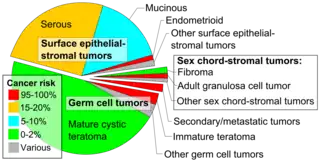

Histopathologic classification

Ovarian tumors are classified according to the histology of the tumor, obtained in a pathology report. Histology dictates many aspects of clinical treatment, management, and prognosis.

The most common forms are:

| Type | Subtype | Relative incidence[2] | Percent malignant[2] | Comments | Micrograph |

|---|---|---|---|---|---|

| Germ cell tumor | Mature cystic teratoma | 46.0% | 0.17% to 2%[3] | Cystic, with elements of all 3 germ layers (endoderm, mesoderm and ectoderm).[4] | .jpg.webp) Hair follicles. |

| Immature teratoma | 2.5% | 100% | A teratoma that contains anaplastic immature elements, and is often synonymous with malignant teratoma.[5] |  | |

| Other germ cell tumors | 3.0% | Others mainly include dysgerminoma, yolk sac tumor, struma ovarii and squamous cell carcinoma arising from a dermoid cyst, and malignant mixed germ cell tumor.[2] | |||

| Surface epithelial-stromal tumor | Serous tumor | 25% | 18.5% | Benign serous tumors of the right ovarian cyst are thinwalled unilocular cysts that are lined by ciliated pseudostratified cuboidal or columnar epithelium.[6] |  |

| Mucinous tumor | 15% | 8.8% | Benign mucinous tumors of the ovary consist of simple, nonstratified columnar epithelium with basally-located hyperchromatic nuclei and resemble gastric foveolar epithelium.[6] |  | |

| Endometrioid tumor | 1% | Almost 100% | Tubular glands, resembling endometrium.[7] |  | |

| Other surface-epithelial tumors | 1.5% | Others include mainly malignant mixed Müllerian tumor, Brenner tumor and mixed epithelial tumor.[2] | |||

| Sex cord-stromal tumor | Ovarian fibroma | 1.5% | 0% | Spindle-shaped fibroblastic cells and abundant collagen.[8] |  |

| Adult granulosa cell tumor | 1% | Almost 100% | Small, bland, cuboidal to polygonal cells in various patterns.[9] | .jpg.webp) | |

| Other sex cord-stromal tumors | 1% | Others include mainly juvenile granulosa cell tumor, thecoma and sclerosing stromal tumor[2] | |||

| Secondary/metastatic) tumor | 2% | 100% | Usually from breast cancer, colon cancer, endometrial cancer, stomach cancer or cervical cancer.[10] | ||

Mixed tumors contain elements of more than one of the above classes of tumor histology.